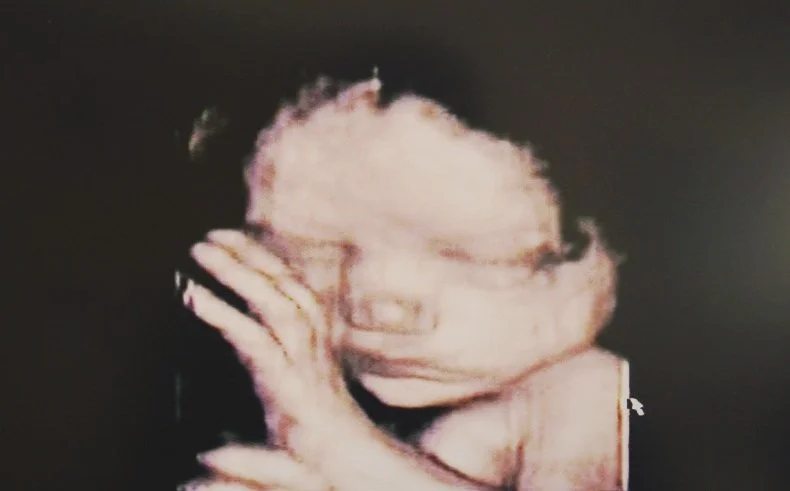

Abortion pills kill children. Approximately 642,700 chemical (abortion pill) abortions were recorded within the formal healthcare system alone, according to the most recent national estimates available. To respond to this changing landscape, the pro-life movement must engage in the battle for life through both culture and policy at every level of government.

All Human Life Deserves Respect: IVF Doesn’t Change That

We must support the creation and well-being of families while respecting the basic human rights of every member of the family, regardless of their age.